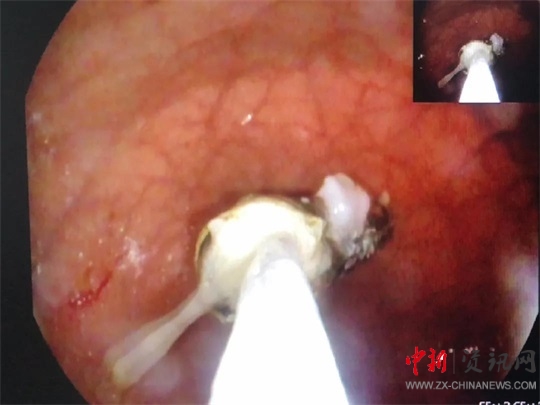

全身麻醉后,醫(yī)生龔靈輝操作胃鏡進(jìn)入孩子胃部,發(fā)現(xiàn)一節(jié)電池浸在胃液里。由于患兒年齡小,胃部體積也很小,長(zhǎng)達(dá)5cm的電池顯得特別巨大,同時(shí)胃鏡下的操作空間也很有限,為手術(shù)帶來(lái)了不小的麻煩。

在手術(shù)過(guò)程中,患兒多次血氧飽和度直下,醫(yī)生不得已拔出胃鏡,進(jìn)行搶救,情況十分危險(xiǎn)。因電池較長(zhǎng),在取的過(guò)程中,幾次卡在食管里。為了防止劃傷食管,龔靈輝不停地變換鏡子的角度,最終找到一個(gè)合適的角度下了圈套器,在護(hù)士宋惠澤和麻醉科醫(yī)生岳娟娟的配合下,歷經(jīng)十幾分鐘把電池像網(wǎng)魚(yú)一樣“網(wǎng)”了出來(lái)。孩子面色紅潤(rùn),生命體征平穩(wěn),手術(shù)順利結(jié)束,所有人都松了一口氣。